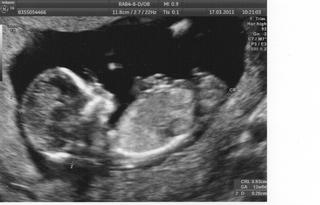

holky dnes sem byla na té genetice na utz-je to v pořádku 🙂 🙂 🙂když sem mimi uviděla,tak se mně tak ulevilo,a když doktor řekl,že je to v pořádku,tak sem se tam radostí rozbrečela,doktor se uculoval a sestřičky se smály 😀

bylo to krásný,dokonce víme co to bude...chlapeček-budeme muset nakoupit modrou výbavičku 😀